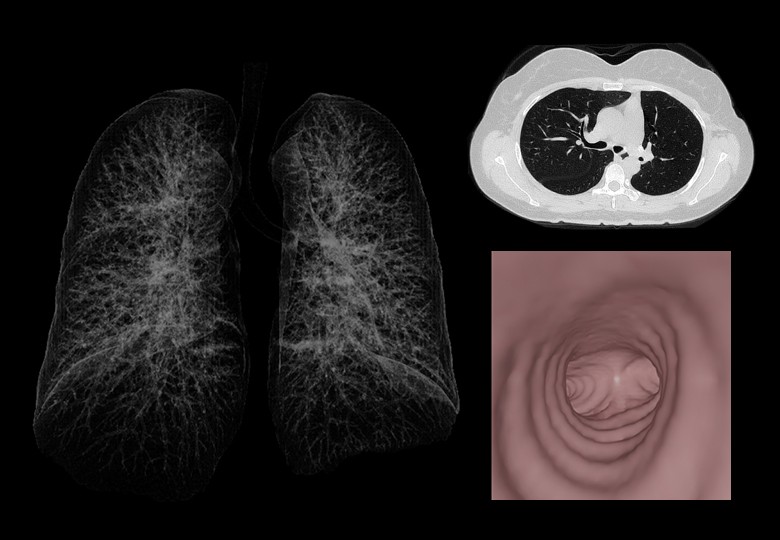

Lung Scan